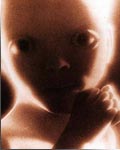

La réunion annuelle de l’ESHRE (European Society of Human Reproduction and Embryology) qui s’est tenue en 2012 à Istanbul (1er au 4 juillet) a donné l’occasion à quelque 9 000 spécialistes de s’informer et de discuter des derniers progrès en médecine reproductive, un domaine scientifique et clinique des « plus excitants » selon le qualificatif de l’actuel président, le Dr Luca Gianaroli. Et de rappeler que près de 5 % des enfants dans certains pays européens sont nés grâce à l’assistance médicale à la procréation et qu’il ne se passe pas de mois sans qu’on annonce une première en la matière, soulevant à chaque fois des débats passionnés. Mais voici quelques échos d’interventions sur des questions sans doute plus pragmatiques.